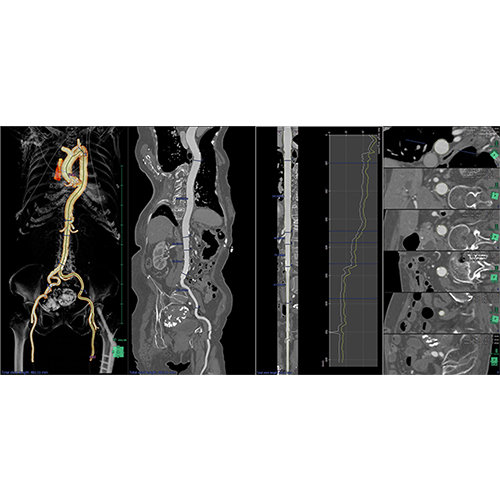

ANYTHINK 经导管主动脉瓣膜置换术分析系统